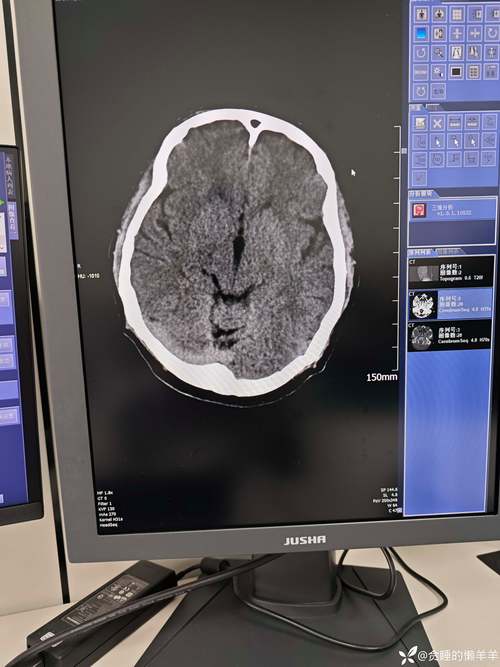

体育资讯3月22日讯 在今天凌晨进行的西甲联赛,瓦伦西亚队长加亚头部被连续撞击两次后离场,并送到医院检查。

加亚随即被送往医院接受了检查,初步结果并无大碍,预计将在得到医院批准后出院返回球队。瓦伦西亚主帅卡洛斯·科贝兰赛后表示:“加亚当时无法继续比赛,因为冲撞导致他有些恍惚。”